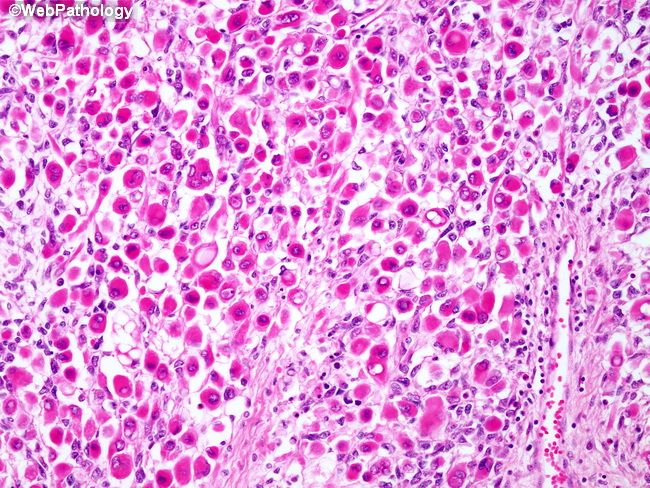

Плеоморфный рак

Плеоморфный рак 113 фото